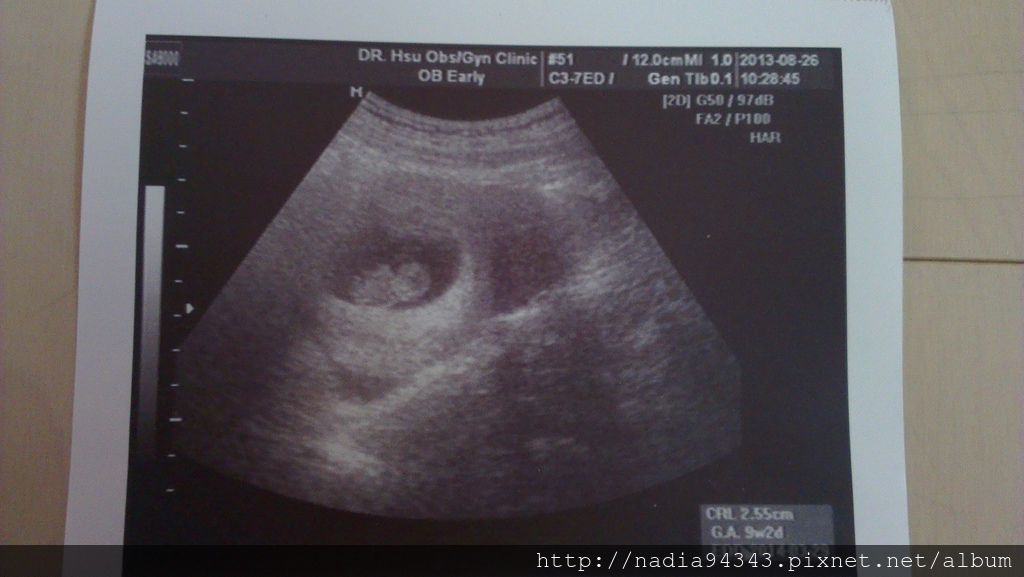

懷孕日記-W5 胚囊照

懷孕日記-W6~W7 心跳

懷孕日記-W8~W9 嚴重害喜/媽媽手冊/澎湖

懷孕日記-W10~W12 日月潭/仍舊害喜

懷孕日記-W13~W16 初唐頸部透明帶/台兒診所早期妊娠評估